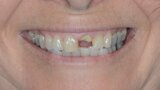

Fig. 1: Initial situation, extra-oral view.